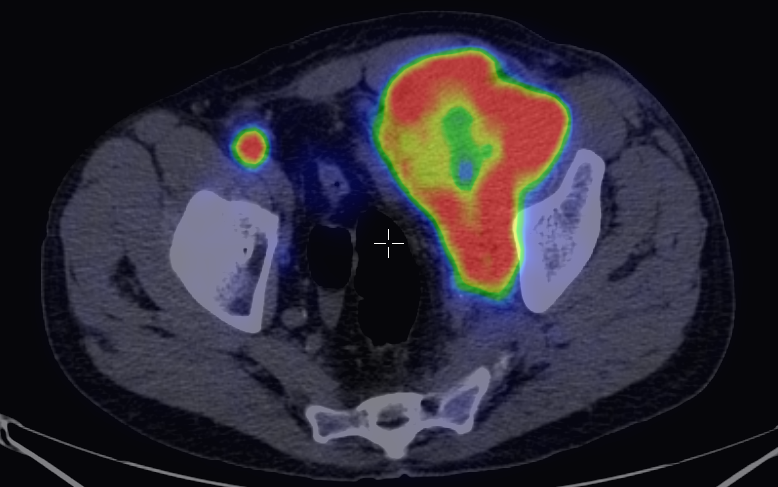

The most common clinical use of FDG-PET is in the form of whole-body scan, with oncologic indications. The majority of malignant tumors operate with higher energy consumption and show an increased glucose metabolism, consequently an increased uptake of FDG. The grade of malignancy is usually proportional to the rate of uptake. This method is useful in oncologic diagnostics, since it is capable to differentiate benign lesions from malignant ones. Whole-body PET imaging is capable to detect the primary tumor with local nodal metastases as well as distant metastatic lesions (staging) in one examination. (Figure 10.)

10. Ewing’s sarcoma in the right humerus. Staging FDG PET-CT. PET Maximum Intensity Projection (MIP) image (a), transversal (b,c) and coronal (d) plane fused PET-CT images. Multiplex metastatic process with nodal, lung and bone involvement.

In the staging of malignant diseases FDG-PET is extremely important, since it has a greater sensitivity and specificity than the morphologic imaging modalities.

This is most certainly true in case of imaging metastatic lymph nodes. Morphological imaging methods utilize size as the only reliable criteria for the differentiation of a metastatic lymph node. FDG-PET detects metabolic changes in the metastatic lesions independently of their actual size. This way, normal sized metastatic lymph nodes can be identified, as well. Larger lymph nodes that are non-metastatic in nature, but for other reasons show abnormal enlargement can also be differentiated. (Figure 11.)